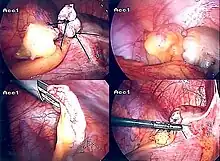

The surgical procedure for the removal of the appendix is called an appendectomy. Appendectomy can be performed through open or laparoscopic surgery. Laparoscopic appendectomy has several advantages over open appendectomy as an intervention for acute appendicitis.[72]

Laparoscopic appendectomy

Laparoscopic appendectomy has become an increasingly prevalent intervention for acute appendicitis since its introduction in 1983.[76] This surgical procedure consists of making three to four incisions in the abdomen, each 0.25 to 0.5 inches (6.4 to 12.7 mm) long. This type of appendectomy is made by inserting a special surgical tool called a laparoscope into one of the incisions. The laparoscope is connected to a monitor outside the person's body, and it is designed to help the surgeon to inspect the infected area in the abdomen. The other two incisions are made for the specific removal of the appendix by using surgical instruments. Laparoscopic surgery requires general anesthesia, and it can last up to two hours. Laparoscopic appendectomy has several advantages over open appendectomy, including a shorter post-operative recovery, less post-operative pain, and lower superficial surgical site infection rate. However, the occurrence of an intra-abdominal abscess is almost three times more prevalent in laparoscopic appendectomy than open appendectomy.[77]